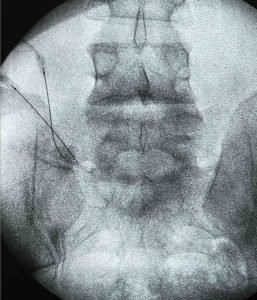

Hola doctor le escribo desde Colombia, lelvo una semana con con dolores desde el gluteo izquierdo y me baja hasta el pie y dedos los cuales siento todo el tiempo como encalambrados, fui al medico y me mando unos rayos X y me salio esto de resultado.

Radiografía de articulaciones sacroilíacas

Hallazgos

Las articulaciones sacro ilíacas son normales.

Los espacios articulares tienen amplitud normal y no se ve esclerosis subcondral. No hay sacroiliítis.

Lo observable de articulaciones coxofemorales también es normal

Mega apófisis transversas en forma bilateral a nivel del último cuerpo lumbar, con neoarticulación y esclerosis a sacro en el lado izquierdo y en relación con segmento transicional

En las estructuras óseas no hay lesiones traumáticas, tumorales ni infecciosas.

En los tejidos blandos no hay masas ni calcificaciones.

Ademas de la radiografía necesitas una resonancia magnética lumbar.

Un saludo